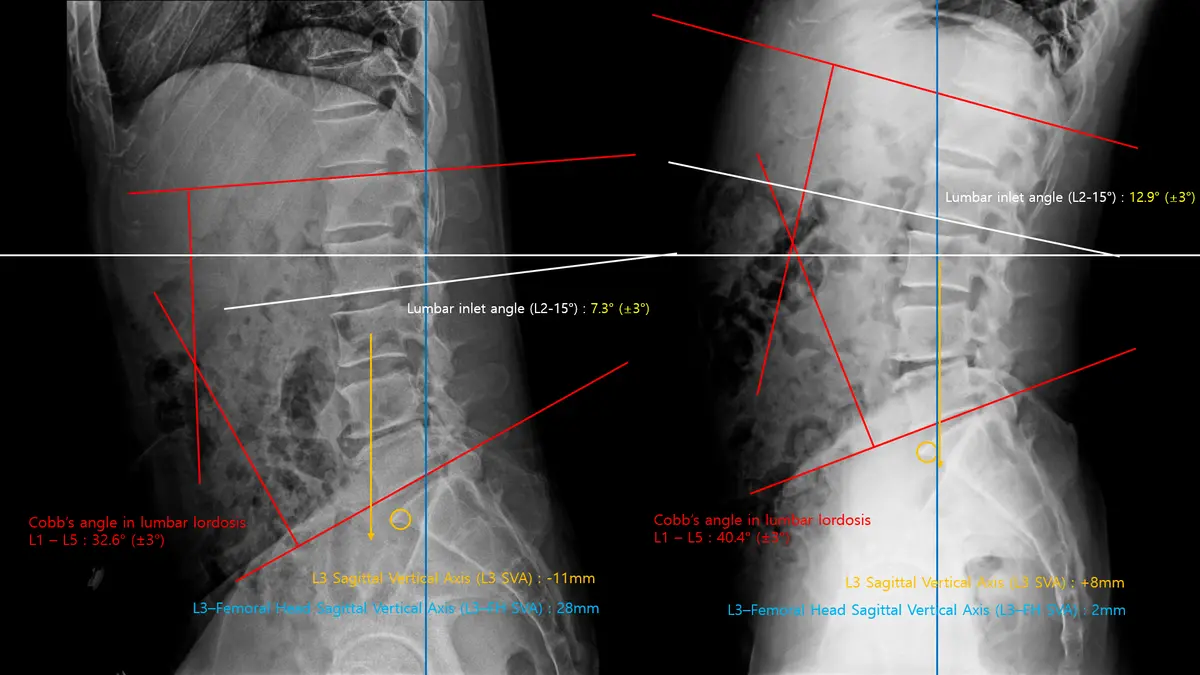

혹시 통증 때문에 운동을 시작했지만, 오히려 더 불편해지거나 나아지지 않는 경험을 해보셨나요? 많은 분들이 근력 부족을 문제로 생각하지만, 사실 통증의 근본 원인은 몸의 '움직임 구조'에 숨어있는 경우가 많습니다. 저희 닥터바디재활운동센터는 동종업계 상위 0.1% 전문가의 정밀한 평가를 통해 고객님 개개인의 고유한 움직임 문제를 정확히 찾아내고, 지속 가능한 변화를 만드는 맞춤형 재활 필라테스를 제공합니다. 저희 센터는 단순한 운동 지도를 넘어, 재활 분야에서 깊이 있는 전문성을 갖춘 책임 교수님과 숙련된 팀원들이 함께합니다. 부산대 물리치료학과 교수, 국가 교육사업 메인강사 등 화려한 경력과 다수의 논문 발표, 실제 현장 노하우로 고객님의 몸을 가장 정확히 분석합니다. '동종업계 상위 0.1% 전문가'라는 자부심으로, 운동의 기초부터 다시 세우는 체계적인 접근을 약속드립니다. 저희 재활 필라테스의 핵심은 '정확한 평가'입니다. 육안으로 확인 어려운 신체 내부 움직임 구조와 불균형을 X-ray 같은 과학적 분석으로 명확히 진단합니다. 척추측만증 Cobb angle이 50도에서 35도로 개선된 사례처럼, 눈에 보이는 변화뿐 아니라 근본적인 신체 구조 회복을 목표로 합니다. 객관적 데이터를 바탕으로 고객님께 가장 필요한 맞춤 솔루션을 제공하여, 통증 없는 건강한 움직임을 되찾아 드립니다. 개개인의 몸 상태에 맞춰 다양한 전문 장비를 활용한 1:1 맞춤 트레이닝을 진행합니다. 레드코드(Redcord) 같은 첨단 슬링 운동 장비로 불안정한 코어 근육을 강화하고, 저항 밴드나 케틀벨로 기능적인 움직임을 회복시키는 훈련을 병행합니다. 단순히 근력을 키우는 것을 넘어, 몸의 협응력과 균형 감각을 향상시켜 일상생활에서의 올바른 자세와 움직임을 자연스럽게 습득하도록 돕습니다. 고객님의 몸이 스스로 최적의 움직임을 찾아갈 수 있도록 섬세하게 설계됩니다. 저희는 고객님 스스로 자신의 몸을 이해하고 관리할 수 있도록 교육에도 힘씁니다. 해부학적 지식, 운동 역학, 다양한 재활 기법에 대한 심도 깊은 강의와 워크숍을 통해 고객님뿐만 아니라 전문가들에게도 올바른 지식을 전달합니다. 이러한 교육적 접근은 고객님께서 운동의 원리를 이해하고, 장기적으로 건강한 생활 습관을 유지하는 데 필수적입니다. 단순히 운동을 시키는 것이 아니라, 몸에 대한 이해를 높여 스스로 건강을 지킬 수 있는 힘을 길러드립니다. 재활 과정은 때로는 힘들고 지칠 수 있습니다. 하지만 저희는 고객님과의 따뜻한 소통과 긍정적인 상호작용을 통해 즐겁고 효과적인 운동 환경을 조성합니다. 고객님의 작은 변화에도 진심으로 공감하고 격려하며, 운동이 단순한 숙제가 아닌 즐거운 일상이 될 수 있도록 돕습니다. '운동의 기초부터 다시 세운다'는 마음으로, 고객님 한 분 한 분의 이야기에 귀 기울이며 최선을 다해 지원합니다. 통증 없는 건강한 삶, 그리고 활기찬 일상은 누구에게나 소중합니다. 저희 닥터바디재활운동센터는 4~12주간의 체계적인 과정을 통해 고객님의 몸이 가진 잠재력을 깨우고, 통증의 악순환을 끊어 지속 가능한 건강을 선물합니다. 이제 더 이상 통증을 참고 운동하지 마세요. 동종업계 상위 0.1% 전문가와 함께, 당신의 몸이 진정으로 원하는 움직임을 찾아보세요. 건강한 변화, 지금 바로 시작하세요!